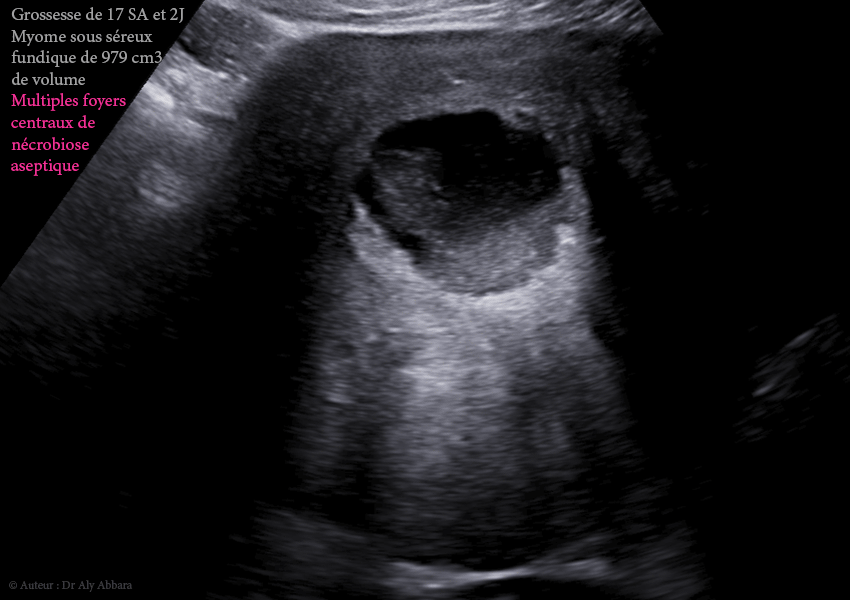

Images échographiques montrant une grossesse intra-utérine évolutive de 17 SA et 2 jours survenant au sein d'un utérus porteur d'un myome sous-séreux fundique (classe 7 de la classification FIGO 2011).

• Il s'agit d'un volumineux myome de 133 x 108 X 131 mm de diamètre, soit = 979 cm3, découvert fortuitement lors de la première échographie de datation (à 10 SA), chez une jeune femme, primipare de 31 ans.

• On remarque échographiquement la présence dans la partie centrale de ce myome, de nombreuses zones liquidiennes aux contours hétéroéchogènes, irréguliers avec un contenu hypoéchogène contenant des résidus diffus ; il s'agit de multiples sites de nécrobiose aseptique enkystés

(dégénérescence kystique partielle du myome utérin).

• À 17 SA : foyers de nécrobiose aseptique centraux (979 cm3).